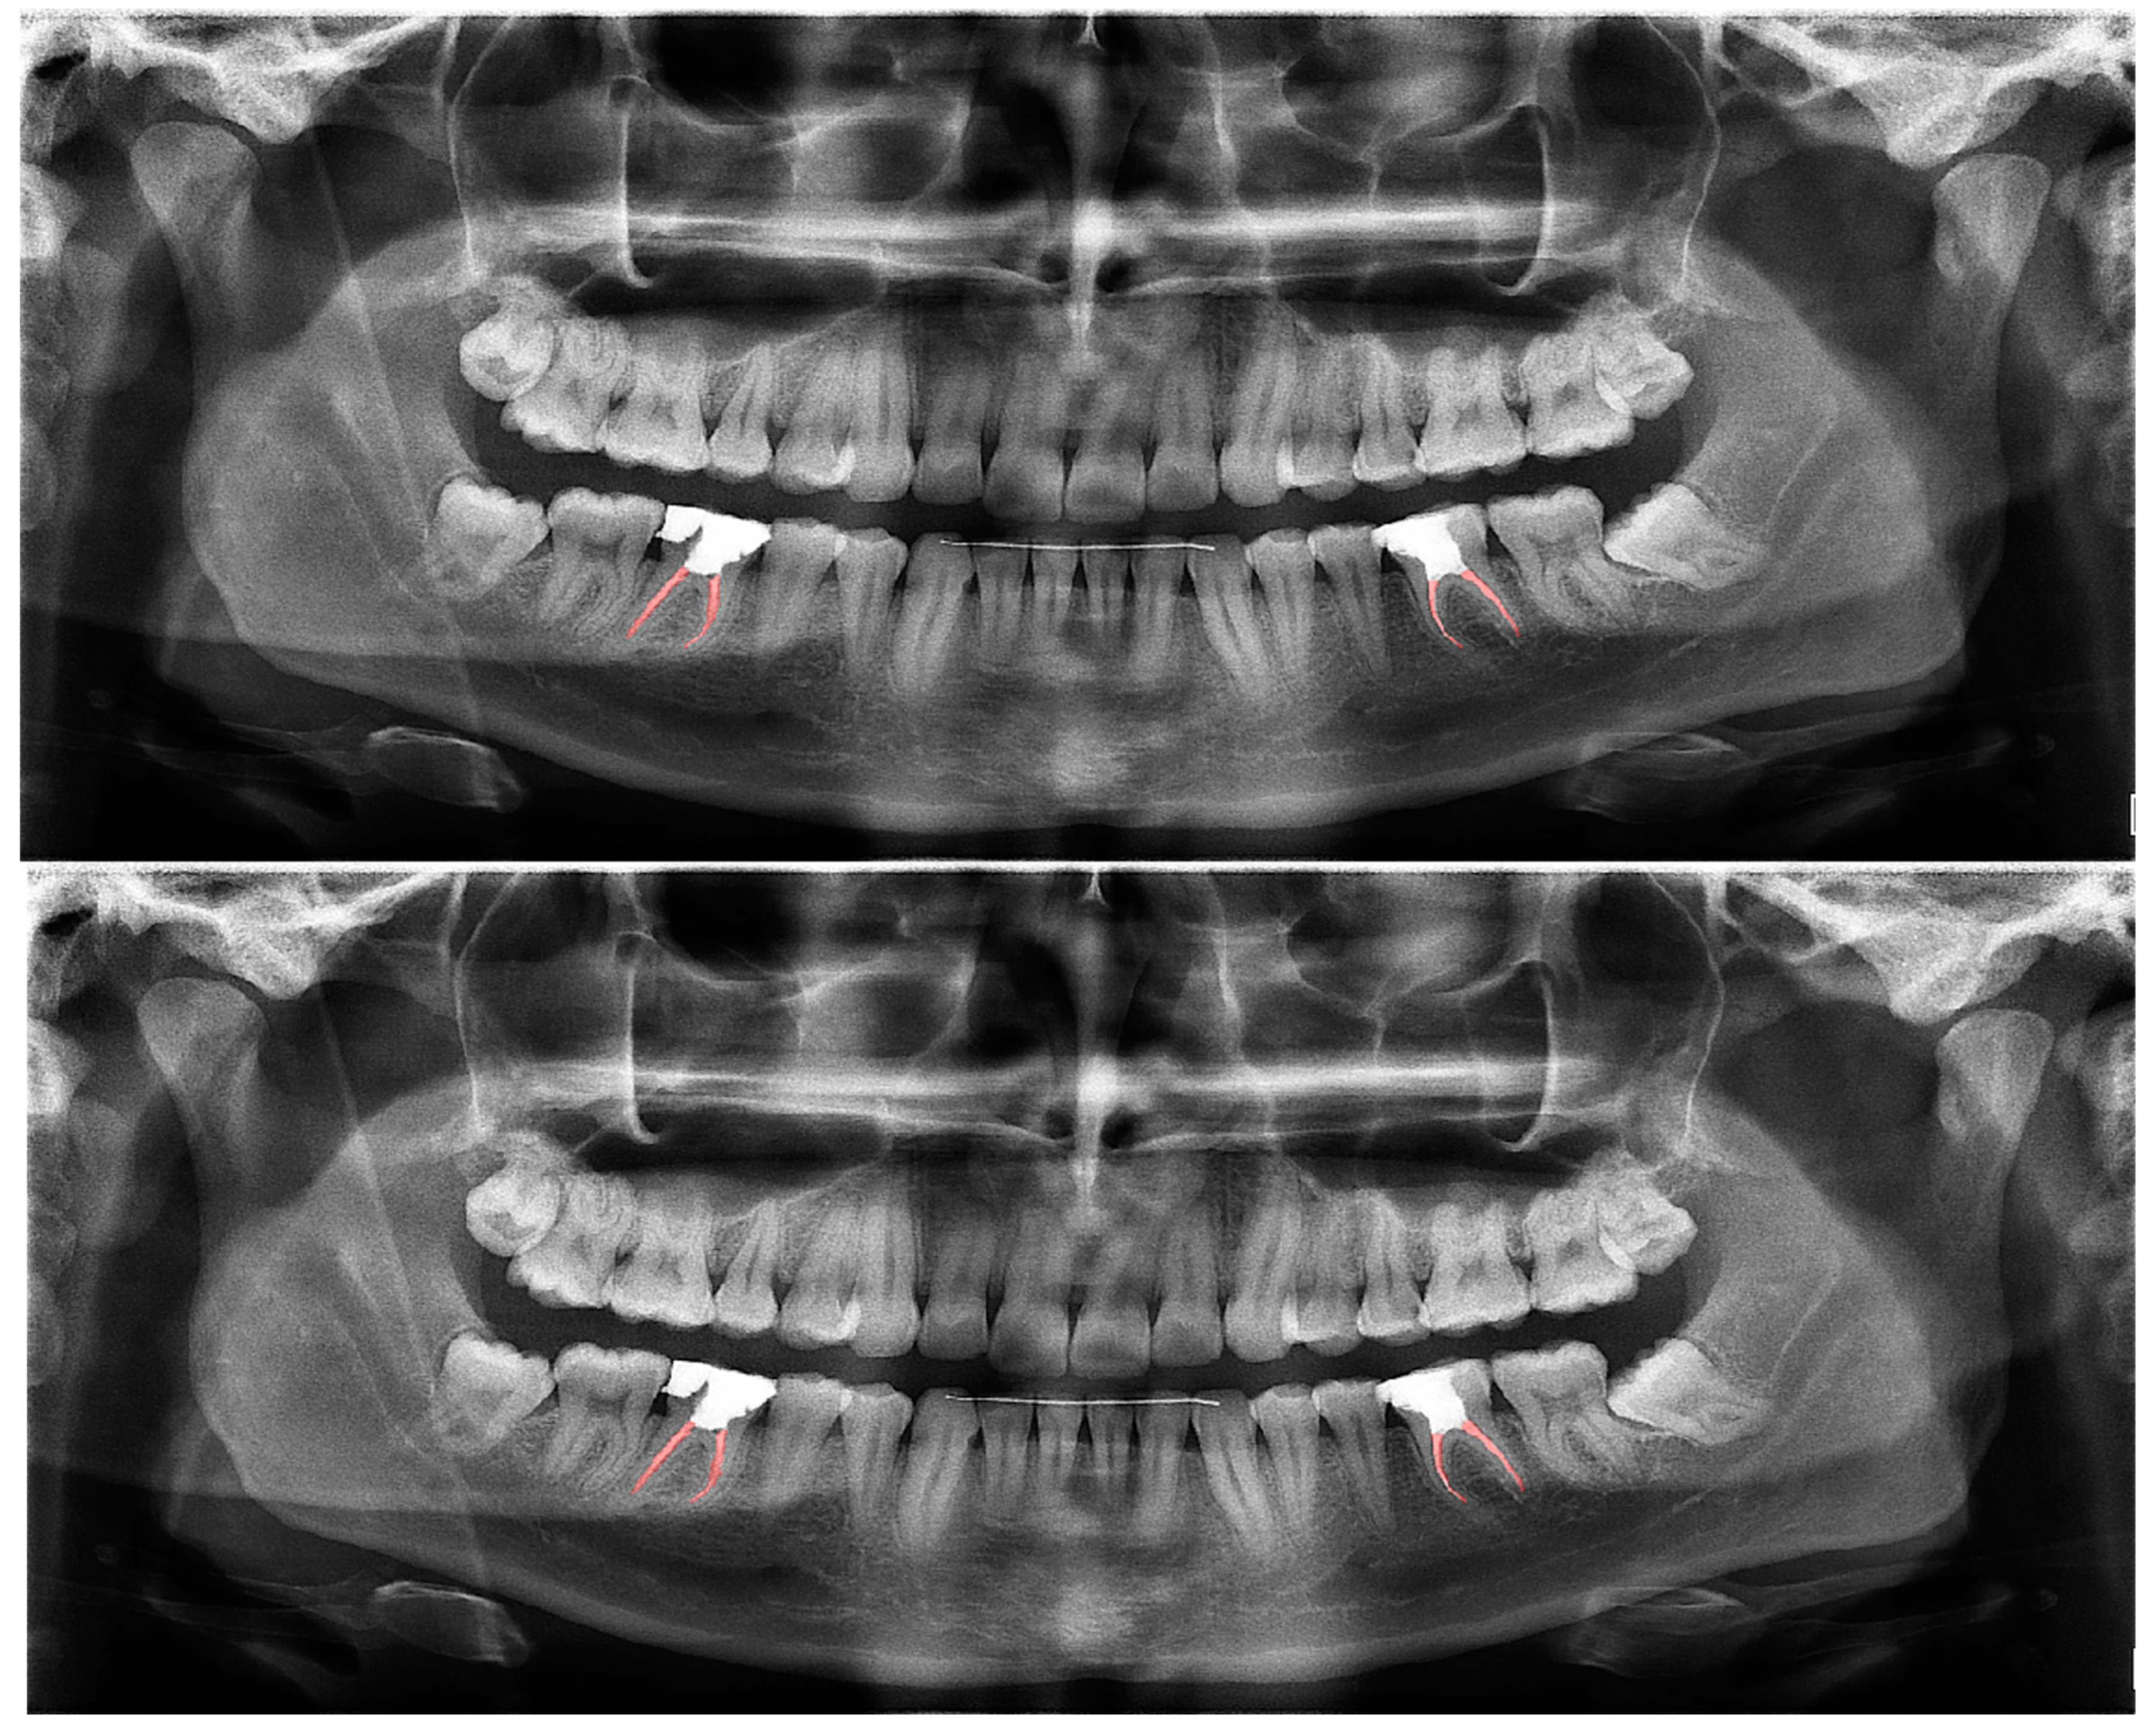

Figure 2.

Automatic segmentation of the teeth. Manual segmentation (upper image) and automatic segmentation (lower image) can be seen above. Each tooth has a unique label according to FDI World Dental Federation notation.

The calculated DSC values across all OPGs (Table 1) were 0.85 for the teeth, 0.88 for dental caries, 0.87 for dental restorations, 0.93 for crown–bridge restorations, 0.94 for dental implants, 0.78 for root canal fillings, and 0.78 for residual roots. Manual segmentations and successful automatic segmentations of the model are given in Figure 2, Figure 3, Figure 4, Figure 5, Figure 6 and Figure 7, while common erroneous automatic segmentations with the most possible reasons are given in Figure 8, Figure 9, Figure 10, Figure 11 and Figure 12.

In tooth segmentation, it has been observed that the segmentation of the root apices of the maxillary third molars, especially those that are impacted in a vertical position, in cases where the root apices are superimposed with the maxillary sinus floor, is incorrectly automatically segmented at different degrees. This is one of the reasons for erroneous segmentation, which reduced the Dice score in our study, albeit only by a small amount. The superposition, which we have seen especially in the premolar region on OPGs, actually shows a limitation of OPGs, not a deficiency of our model (Figure 9). The primary reason why our model could not achieve a perfect result in tooth segmentation is because it is almost impossible to avoid superimpositions on OPGs, especially in premolar teeth, and also because patients with crowding are included in the study. Several studies excluded patients with orthodontic problems; however, one of our main goals was to evaluate the success of our model in the general population, since there will not be any exclusions in dental clinics [91,92].